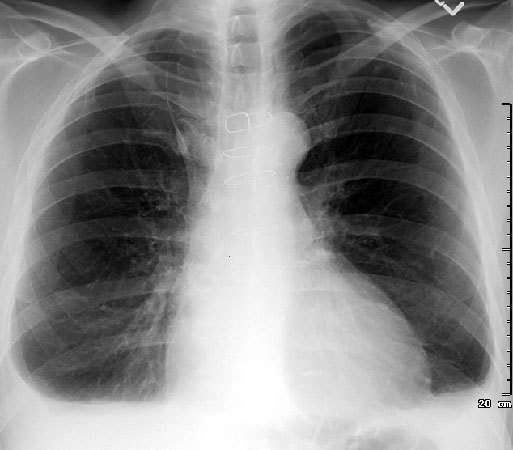

Describe the abnormality/ies

Cannonball metastases (most commonly from renal cell carcinoma)